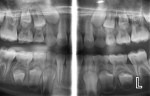

Some clinicians are not aware that they can take high-resolution (7-8 line pairs/mm) extraoral/panoramic bitewings. Dentists with pediatric patients may never have to put another image receptor in a child’s mouth again, and periodontists can take vertical bitewings without positioning problems. This is because several manufacturers now make panoramic machines that have bitewing programs. The disadvantage of the panoramic image for caries detection in the past has been inadequate line pair resolution and overlap of the contact points in the bicuspid regions. These deficiencies are now a thing of the past. One manufacturer (Planmeca, www.planmecausa.com) offers a patented technology called Selectively Compliant Articulating Robotic Arm (SCARA). The only machine to have a C arm on the top of its carriage, the bitewing acquisition is done robotically, with the patient in a typical panoramic position and the carriage moving inward toward the patient with a different start position to open contacts on most patients (Figure 1 through Figure 5). Of course, as with any dentition, if the tooth is ectopic or rotated, an additional image may be necessary to open the contacts. However, the quality of the image and ease of acquisition make this a very attractive technology. Looking carefully at the images, it is apparent that they are not only high-quality interproximal bitewing X-rays, but also high-quality periapical images from the canine to the molar region. Thus, with a digital panoramic machine capable of bitewing projections and producing excellent initial periapical views, the dose to the patient will be lower in most cases by eliminating unnecessary intraoral images. Although it is not a replacement technique, several dental schools in North America—including the Arizona School of Dentistry & Oral Health (ASDOH)—have adopted the protocol of using a panoramic and the extraoral panoramic bitewing/periapical projection as their initial radiographic examination. In addition, offices using this approach will find that there are fewer retakes and, therefore, less staff frustration related to radiographic procedures. At ASDOH, it has been found to reduce the number of full-mouth X-ray series, and intraoral and supplemental bitewing X-rays are needed only when indicated by selection criteria.

In addition to the possible reduction or even elimination of intraoral images for certain pediatric patients, the examples provided indicate that periodontists requiring vertical bitewings may also be interested in these contemporary panoramic machines.